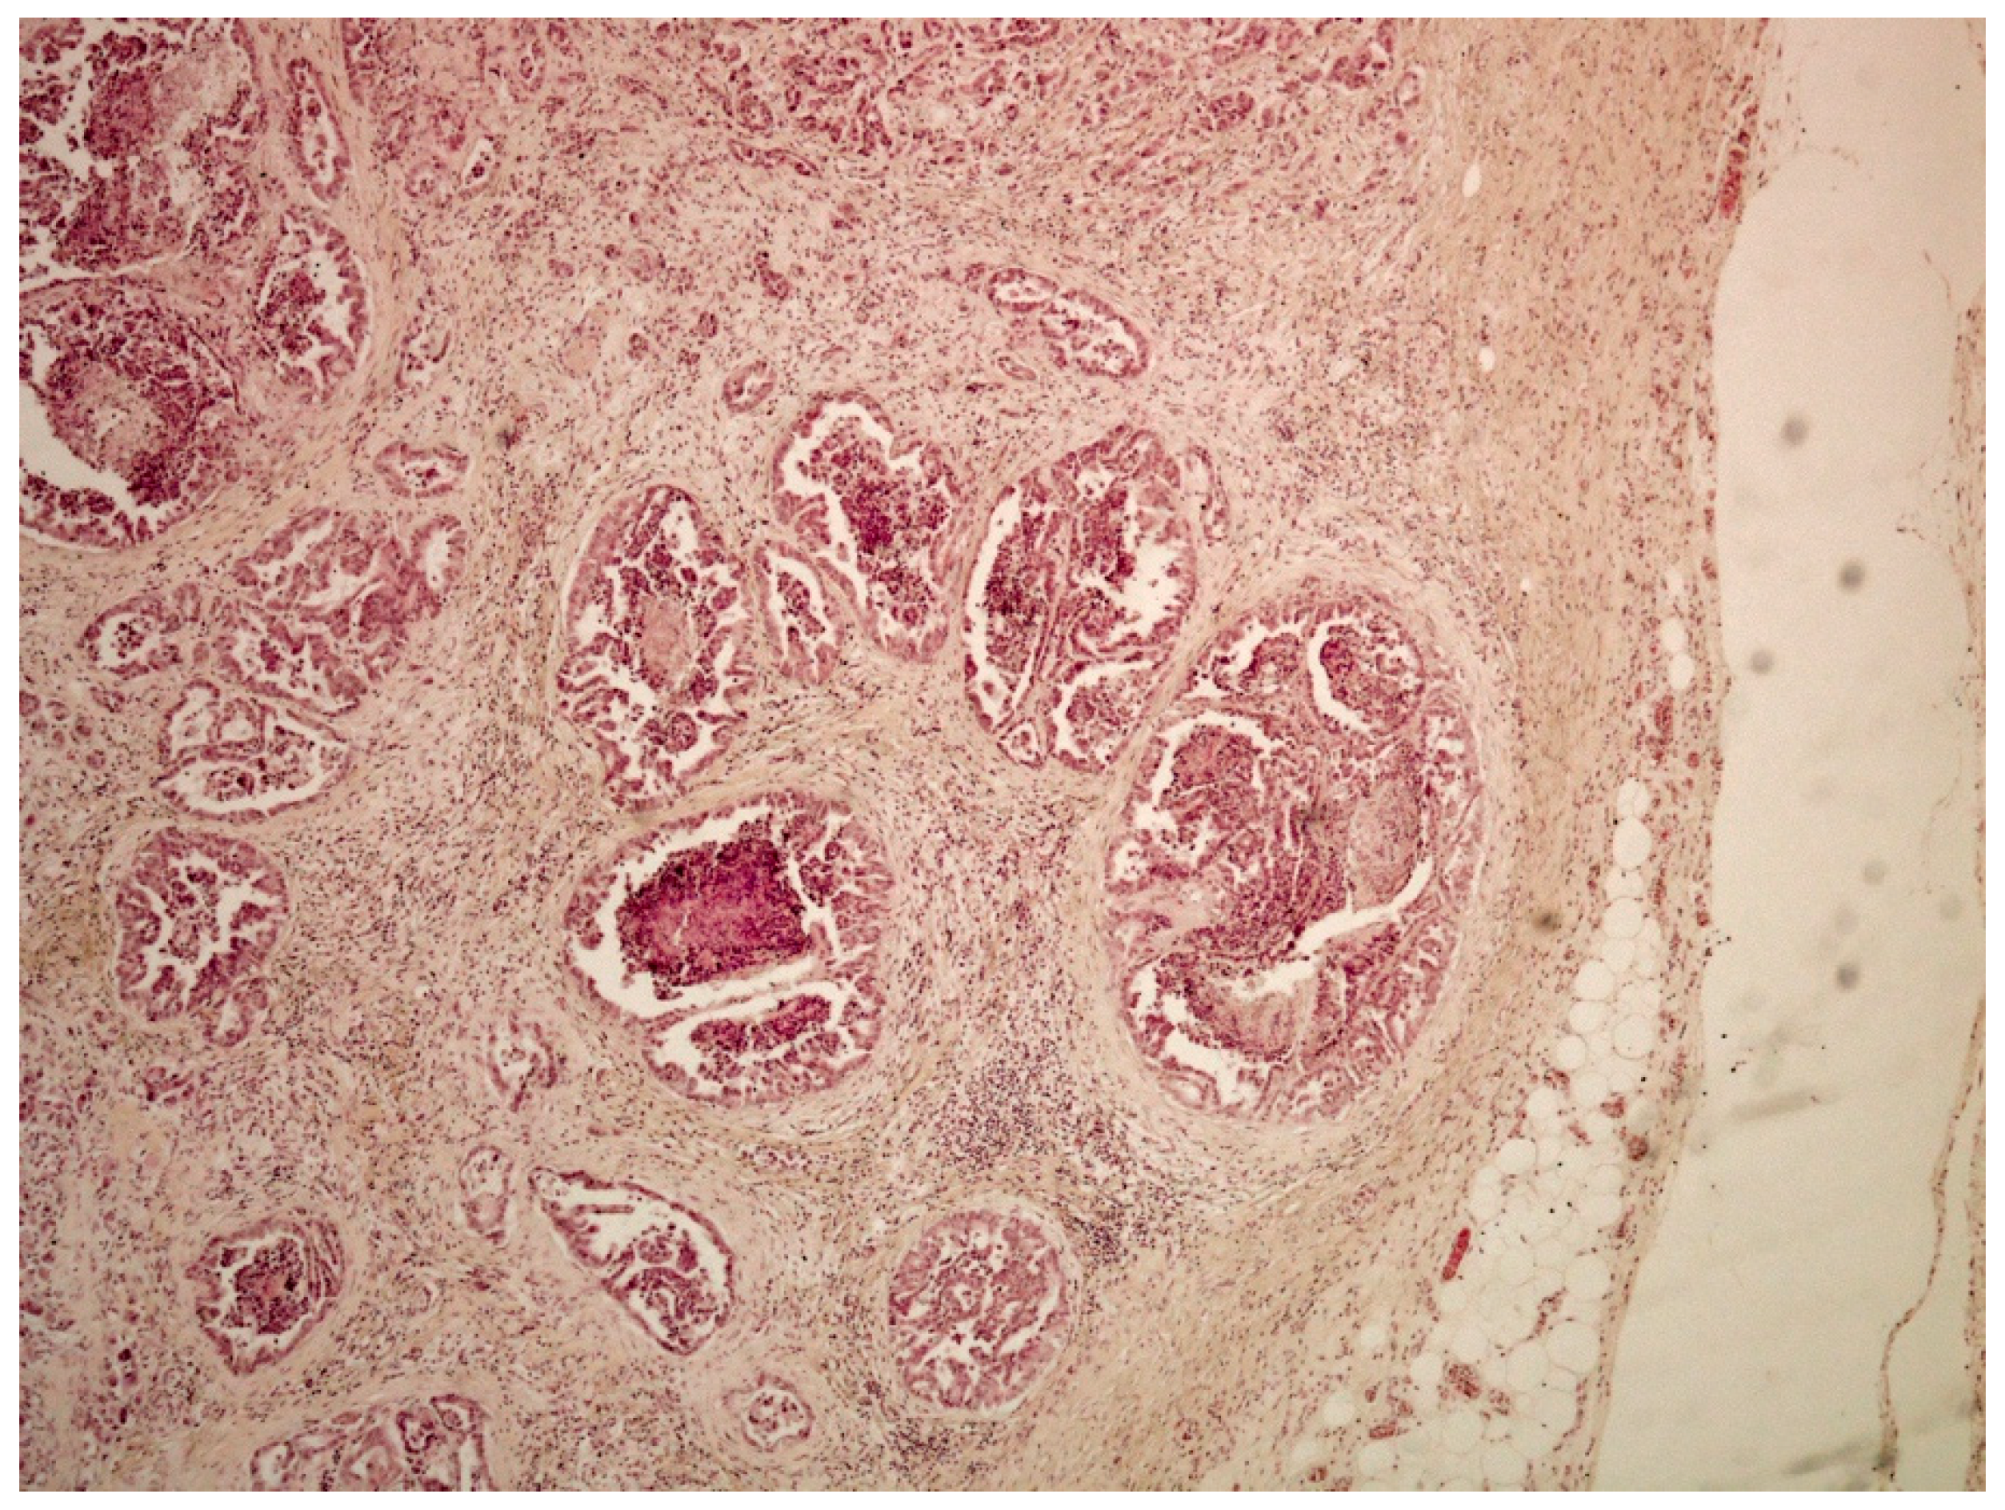

On histological examination (HES stain ×40) (Figure 4), the prostate was invaded and replaced by a poorly defined infiltrative unencapsulated and densely cellular tumor. Tumoral population was arranged in multiple lobules of duct-like structures, lined by unique or multiple layers of pleomorphic neoplastic cells, or occasionally in small clusters of neoplastic cells separated by a plentiful stroma response. Metastatic emboli were numerous. Multiple pulmonary emboli and focal metastatic infiltration with carcinomatous cells (HES stain ×100) (Figure 5) confirmed the severe lymphatic and parenchymatous pulmonary tumor extension, which probably caused the hypertrophic osteopathy. A decalcified longitudinal femur section (HES stain ×40) (Figure 6), showed, from right to left, the cortex, perpendicular bony periosteal trabecular proliferation and an exuberant periosteal reaction characteristic of hypertrophic osteopathy lesions. In addition, several concomitant foci of carcinomatous cells were observed in the medullary cavities of the preexisting bone and in the periosteal proliferation (HES stain ×40) (Figure 7). These observations confirmed the diagnosis of prostatic adenocarcinoma with lymph node, pulmonary, liver and bone metastases, associated with hypertrophic osteopathy.

Figure 4. Prostate invaded by a poorly defined unencapsulated tumor, which is densely cellular and infiltrative (HES stain ×40).